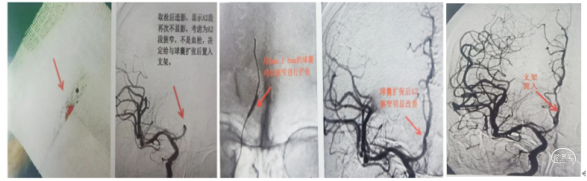

造影右侧大脑前动脉缺如(未发育),左侧大脑前A2段闭塞。

1、微导丝越过闭塞处到达A3段。下图1

2、5F 125中间导管辅助高到位下图2。

3、手推造影明确血栓位置下图3。

4、微导管到达A4段下图4。

5、3*20取栓支架到位回撤微导管,多点显影标记,清晰可见支架打开良好下图5。

造影显示血管再通。

(1)直奔主题,行右侧颈动脉造影,右侧A2原有狭窄处闭塞。下图1。

(2)左侧颈内动脉造影,左侧颈内动脉只供应同侧大脑前动脉、大脑中动脉不向右侧A2代偿供血下图2。

(3)微导管穿过右A2闭塞部位造影,提示A2以远通畅,下图3.

(5)决定取栓1次取出少许血栓,但取栓后造影,右侧A2仍然不显影。下图1、2

(6)微导丝穿过右A2闭塞部位,用2mm的球囊快速交换到达狭窄部位,低压力扩张后造影,可见右A2原有狭窄明显改善。下图3、4

7)把4mmX20mm的solitaire FR支架覆盖A2狭窄部位并解脱支架,造影可见右侧大脑前动脉完成再通,TICI3级,原有狭窄完全消失。下图5